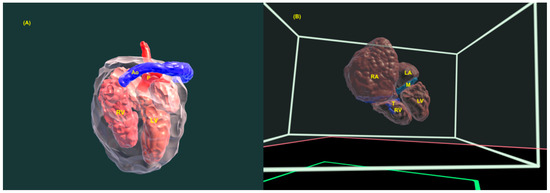

4. Three-Dimensional Physical and Virtual Models of the Fetal Heart

- Werner, H.; Lopes, J.; Ribeiro, G.; Raposo, A.B.; Trajano, E.; Araujo Júnior, E. Three-dimensional virtual traveling navigation and three-dimensional printing models of a normal fetal heart using ultrasonography data. Prenat. Diagn. 2019, 39, 175–177. [Google Scholar] [CrossRef]

- Bravo-Valenzuela, N.J.; Monteiro Pereira Leite, M.F.; Lopes, J.; Arcoverde, V.; Ribeiro, G.; Araujo Júnior, E.; Werner, H. Three-dimensional navigation inside a normal fetal heart in a virtual reality environment. J. Clin. Ultrasound 2024, 52, 1442–1443. [Google Scholar] [CrossRef]

- Giffoni, M.C.; Lopes, J.; Ribeiro, G.; Araujo Júnior, E.; Werner, H. Fetal heart segmentation in a virtual reality environment. Int. J. Cardiovasc. Imaging 2024. online ahead of print. [Google Scholar] [CrossRef]

- Nieblas, C.O.; Bravo-Valenzuela, N.J.; Araujo Júnior, E.; Werner, H. Fetal transposition of the great arteries: 3D virtual and physical models from ultrasound datasets. Int. J. Cardiovasc. Imaging 2024, 40, 1157–1158. [Google Scholar] [CrossRef]

- Pires, G.D.V.; Nieblas, C.O.; Bravo-Valenzuela, N.J.; Araujo Júnior, E.; Castro, P.T.; Werner, H. Ebstein anomaly: 3D virtual and physical models from obstetrical ultrasound data. Echocardiography 2024, 41, e15806. [Google Scholar] [CrossRef] [PubMed]